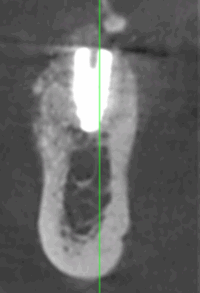

Reprise de traitement implantaire

La reprise de traitement désigne le processus par lequel un patient reprend des soins après un échec de traitement implantaire ou lorsque des complications surviennent. Voici les étapes typiques d’une reprise :

En cas d’échec ou de complications, la reprise de traitement implique une évaluation diagnostique, une extraction (si nécessaire), une cicatrisation, puis une reconstruction osseuse suivie d’une nouvelle implantation.